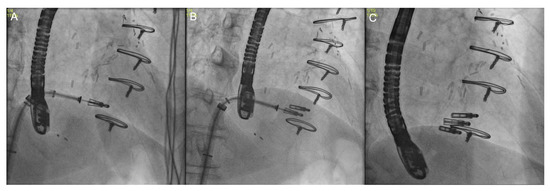

3.4. Fusion Imaging